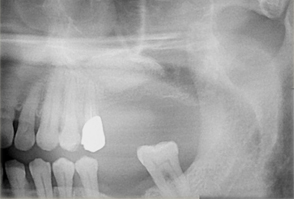

ボーングラフトインプラント(ブロック骨移植をし骨造成をしたインプラント)

ボーングラフトは、十分な量の骨が得られない場合に、骨をブロックで切り出し、移植することで必要な骨を作り出します。

- 主訴

- 上顎前歯の噛む時の痛み

- 治療内容

- 上顎前歯部を抜歯すると大きな骨吸収を予測したため、下顎臼後三角部より骨片を採取し、抜歯時にインプラント埋入と同時に骨造成を行なった

- 治療費用

- 800,000円(税別)

- 治療期間

- 5ヶ月